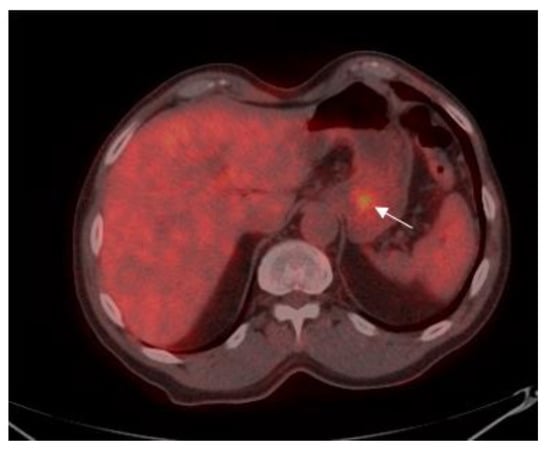

Patients were classified into two groups according to the level of SUV avidity of the primary lesion in the baseline PET-CT: the high-SUV (>3.5) group included 58 (52.3%) patients (Figure 1), and the low-SUV (≤3.5) group included 53 (47.7%) patients (Figure 2).

Figure 1. A 70-year old male with gastric adenocarcinoma (SRCC). Axial PET-CT images show low 18F-fluorine-18 fluoro-2-deoxy-D-glucose (FDG) uptake (standardized uptake value (SUV)max: 16.2) in primary tumor in the body of the stomach (white arrow).